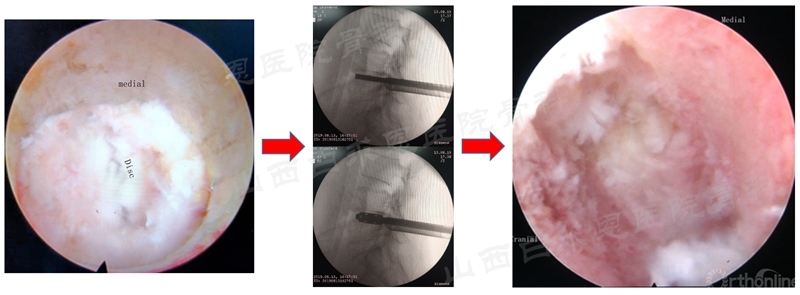

N:Nerve root(神经根);Disc(椎间盘)

(5)椎间盘切除和终板处理

(6)椎间植骨和融合